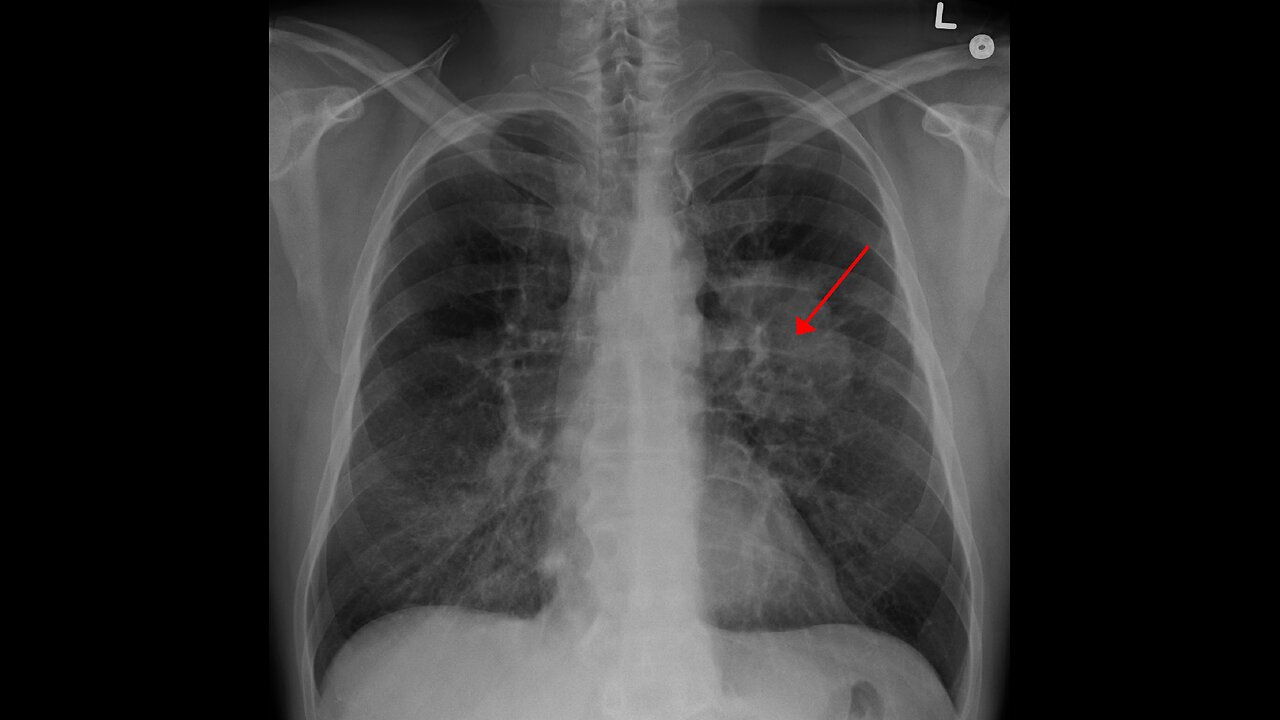

OXYGEN DEPRIVED PEOPLE OFTEN CONTRACT CANCER! IS THERE AN ANTIDODTE? JEFF ADAMS